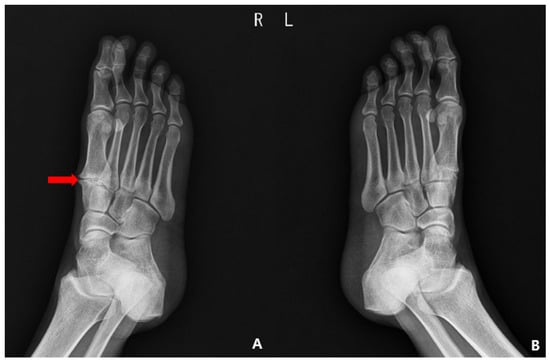

2. Case Presentation

2.1. Preoperative Evaluation